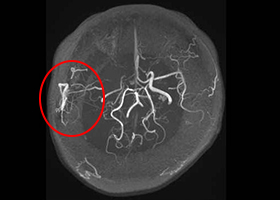

38歳、もやもや病、左半身一過性脳虚血発作

[画像所見]

-

右 頭部MRI -

頭部MRA(脳血管の脱落、赤丸部) 左

[術後画像検査]

術前MRA -

術後MRA

術後はバイパス血管が脳内に向かって出現しています(赤丸印)。